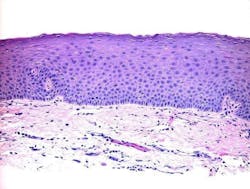

A pathology report was ordered, a deep-shave biopsy was performed, and the nodule removed. Pathology showed the mucus membrane with compressed fibrous tissue within the lamina proper and associated sparse inflammation (figures 3 and 4).

This report describes a lesion of the lower attached gingiva that was definitively diagnosed by histologic examination as a mucocele or mucous retention cyst. The usual location of mucoceles is on the lower lip. However, this case illustrates an uncommon presentation of a mucocele with respect to location.

Mucoceles are benign lesions that are filled with mucus and can appear in the mouth, appendix, paranasal sinuses, lacrimal sac, appendix, or gall bladder.1 Generally, mucoceles occur as a sphere and are asymptomatic. Mucocele is the seventeenth most common salivary gland lesion found in the oral cavity. The clinical appearance is typically a distinct, fluctuant, painless, bluish swelling of the mucosa. Most lesions are smaller than 1 cm in diameter. They form due to mucus accumulating when there is an alteration in the minor salivary gland that leads to limited swelling. Mucoceles typically do not form on the attached gingiva.